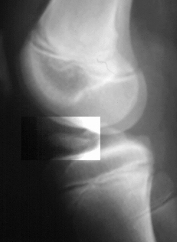

This is a 14 year old male who presented to the emergency room complaining of left knee pain after falling off his bicycle. Examination reveals a swollen left knee. The skin was intact. There was tenderness to palpation diffusely about the knee. Valgus stress at full extension and at 30 degrees revealed an increased laxity on the left. Anterior draw and Lachman tests were also asymmetric with an increased excursion on the left. Neurovascular exam was unremarkable.

This fracture would be best classified as a Type III Meyer's / McKeever tibial spine fracture.

This fracture often fails closed reduction because of soft tissue interposition.

To fully evaluate this fracture prior to treatment an MRI should be obtained.